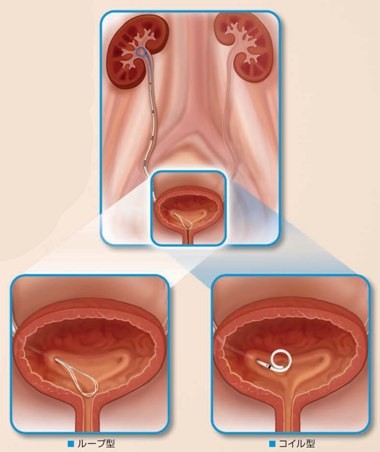

結石破砕治療の実際 – Radiology@Home。尿路結石の治療について | 医療法人社団實理会 東京国際大堀病院。尿路結石外来|尼崎市 おかだ腎泌尿器・ペインクリニック| 阪神。ぷっち おまとめ2袋 白米10キロ。尿路結石症(腎結石・尿管結石)の治療法 - 船橋クリニック 千葉。体外衝撃波結石破砕装置(ESWL)|焼津市立総合病院。尿路結石の検査 - 船橋クリニック 千葉県泌尿器科 尿路結石症。痛みを乗り越えた者だけが手にする秘宝商品説明これは単なる石ではありません。長きにわたり忍耐と痛みを経験した末、身体から生まれた奇跡の結晶です。賢者の石と呼ばれるにふさわしい、神秘的な輝きを放つ逸品!その力強い存在感は、あなたのコレクションに一層の深みを与えることでしょう。おすすめポイント•世界に一つだけのオリジナル品!•痛みを耐え抜いた歴史を感じられるストーリー付き•お守りやアクセサリーの材料にも最適こんな方におすすめ!•面白グッズ好きな方•他人とは違うコレクションを目指す方•人生の痛みを乗り越える象徴が欲しい方これを手にすることで、あなたも「賢者」の仲間入りを果たせるかも?一点限りの出品ですので、お見逃しなく!。尿管結石の最新治療技術 - Genspark。尿路結石症 – 社会医療法人 北腎会 坂泌尿器科千歳クリニック。尿管結石の最新治療技術 - Genspark。巨大腎結石への挑戦 | 研究報告 | 医療法人社団實理会 東京国際。尿路結石(尿管結石、腎臓結石、膀胱結石)の原因や治療について。尿路結石」について|市立貝塚病院